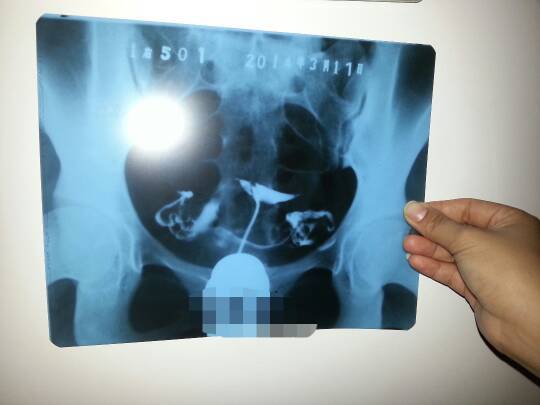

今天做了输卵管造影,请专家帮我看下拍的片子是不是双侧输卵管伞周粘连,如果是的话,会造成不孕不育么?

今天做了输卵管造影,请专家帮我看下拍的片子是不是双侧输卵管伞周粘连,如果是的话,会造成不孕不育么?谢谢!

病情分析: 双侧的输卵管都是畅通的,造影剂已经进入腹腔内了。 指导意见: 但是左侧的造影剂弥散涂布不是太均匀,不除外有轻度粘连。你的这种情况应该不会造成不孕症的。